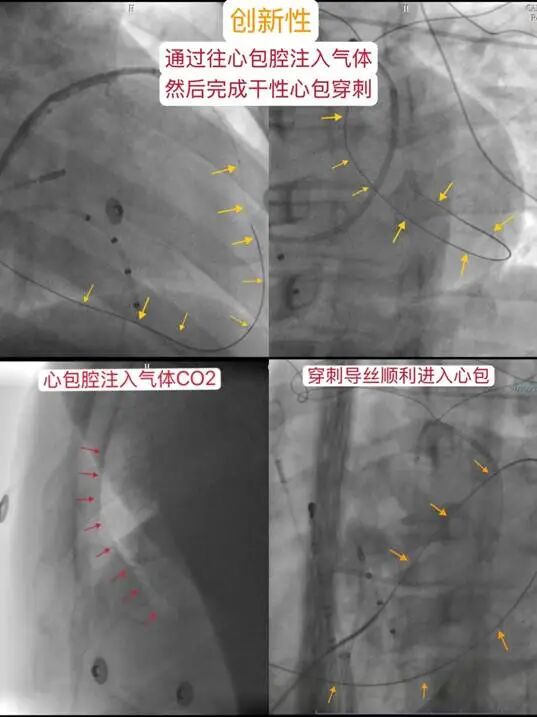

心外膜射頻消融術(shù)被譽為“心臟電生理領(lǐng)域皇冠上的明珠”,技術(shù)難度和風(fēng)險極高。手術(shù)需進行干性心包穿刺建立通路,操作中極易損傷鄰近的肝臟、結(jié)腸、膈肌、心肌、冠狀動脈等重要臟器,國內(nèi)僅極少數(shù)頂尖心律失常中心能夠常規(guī)開展,河北省內(nèi)此前僅滄州市中心醫(yī)院具備此技術(shù)能力。

手術(shù)當日,由心律失??仆鯊┥街魅魏蜕騺喐敝魅喂餐鞯?,袁永剛副主任醫(yī)師及導(dǎo)管室趙明主任、董桐俊護士長、徐超護士長、辛立棟護士長等緊密配合。團隊創(chuàng)新性地應(yīng)用了CO2主動積氣技術(shù),高效、安全地完成了關(guān)鍵的干性心包穿刺,成功建立手術(shù)入路。